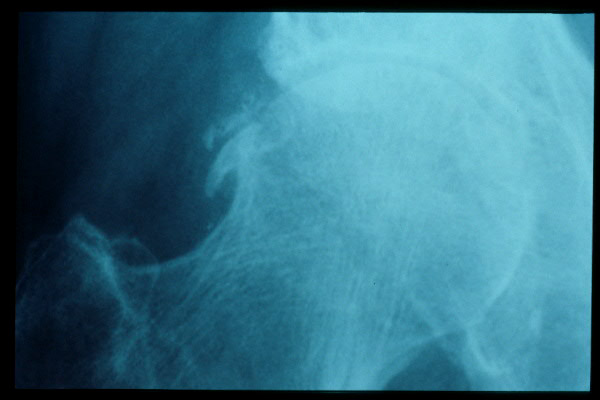

Artrosis avanzada de cadera. Anquilosis.